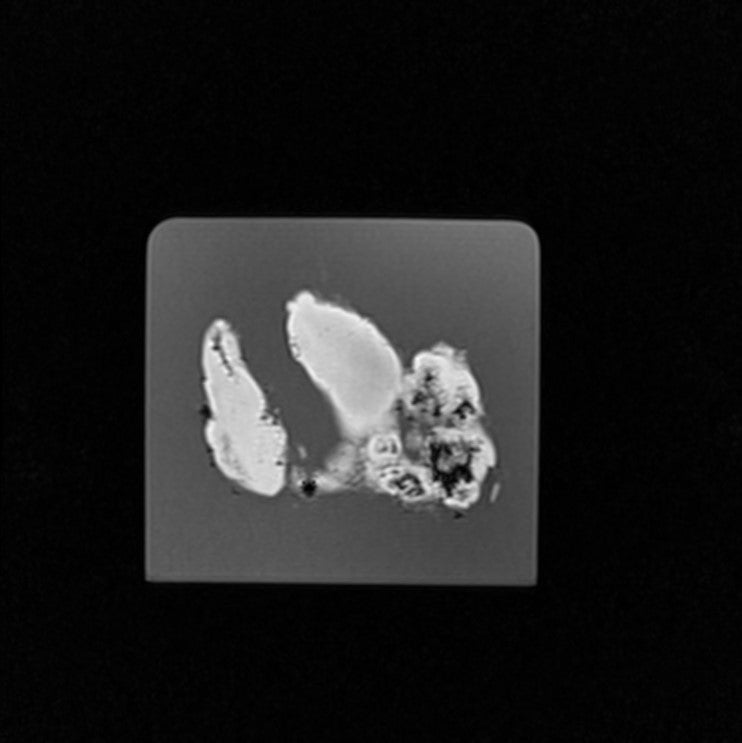

Thyroid - Graves Disease

Radiopath – Thyroid